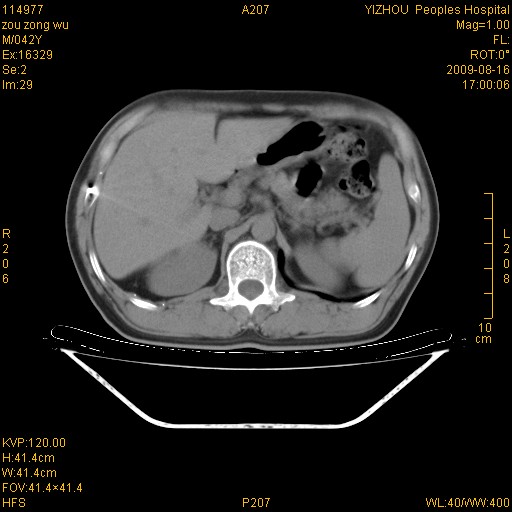

以下是引用zjzjr在2009-8-17 10:42:00的发言:[br]右侧间质性肺炎伴纤维化,右肺下叶肺囊肿伴感染(不除外外伤后引起),右肺野及胸壁软组织\\肝内见多发斑点状,中枪了吧.右侧胸膜肥厚\\粘连.